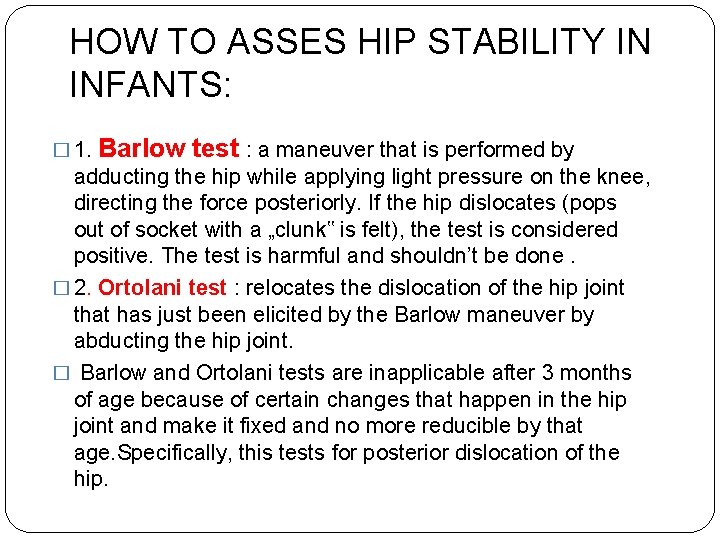

HOW TO ASSES HIP STABILITY IN INFANTS: � 1. Barlow test : a maneuver that is performed by adducting the hip while applying light pressure on the knee, directing the force posteriorly. If the hip dislocates (pops out of socket with a „clunk‟ is felt), the test is considered positive. The test is harmful and shouldn’t be done. � 2. Ortolani test : relocates the dislocation of the hip joint that has just been elicited by the Barlow maneuver by abducting the hip joint. � Barlow and Ortolani tests are inapplicable after 3 months of age because of certain changes that happen in the hip joint and make it fixed and no more reducible by that age. Specifically, this tests for posterior dislocation of the hip.